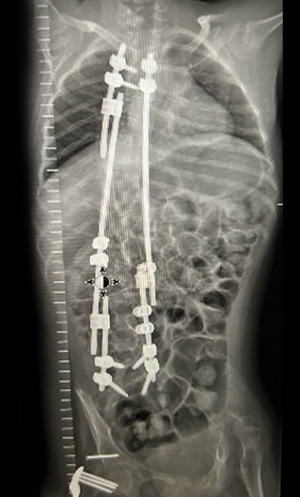

Gallery : Before - After